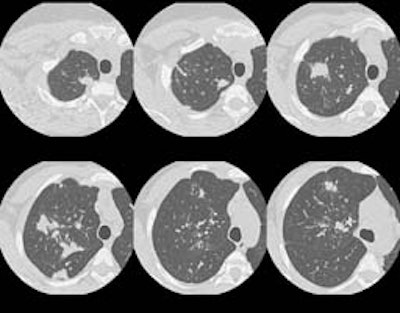

HRCT images:

(Click small pictures to view larger radiographs)